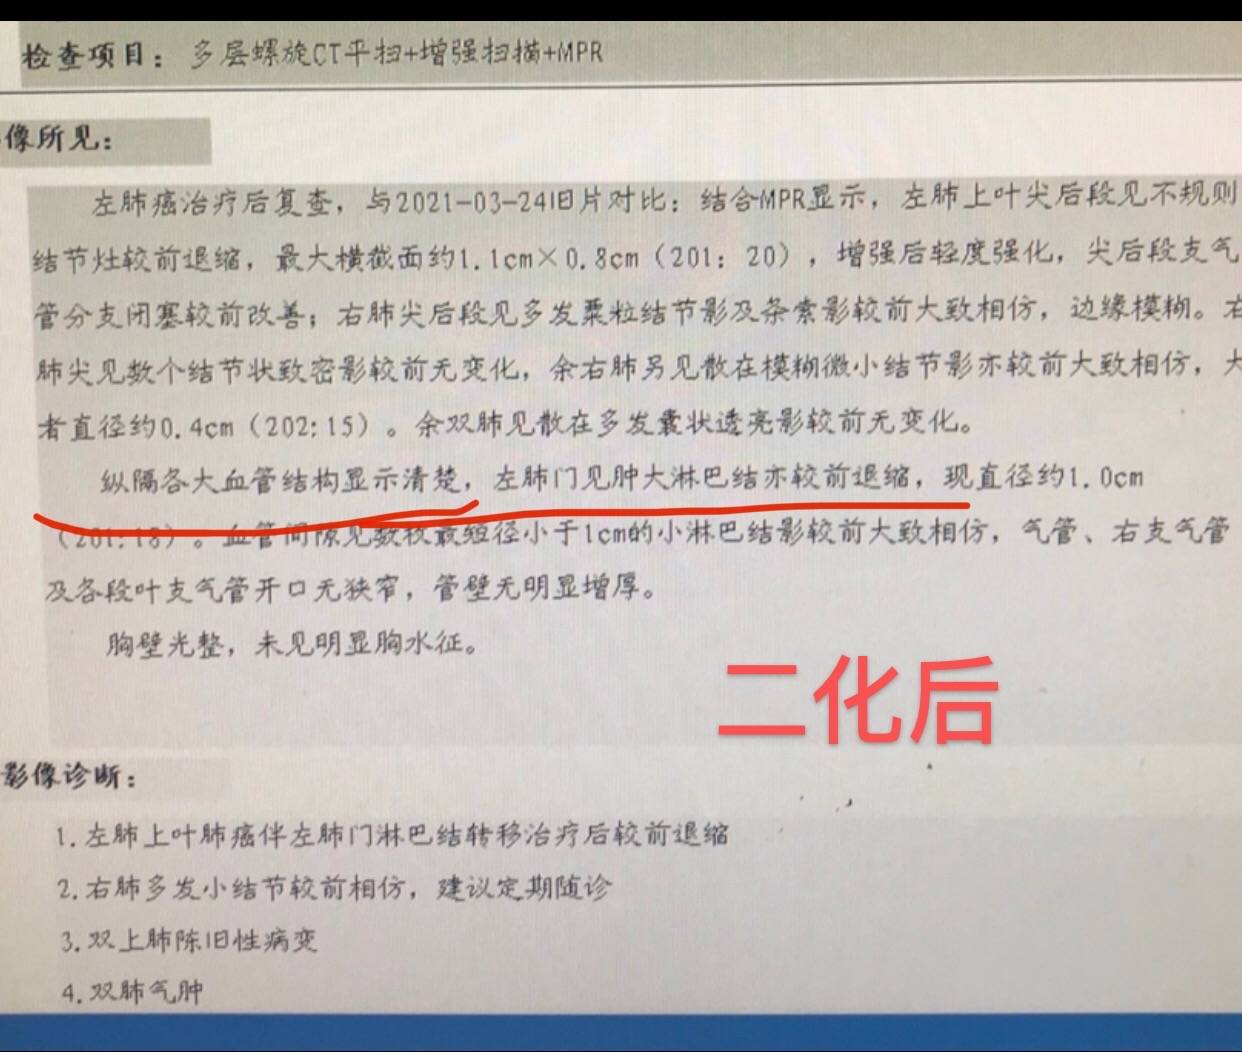

复查效果不错

因为出现心肌酶略增高,三化效果不错,病灶仅剩"少许软组织影"了,故决定抓紧手术。

大家可以注意一下这里,原发灶变成少许软组织影,提示明显变小了,但为什么淋巴结增多,增大呢?

免疫治疗效果很好,淋巴系统激活活跃的话,淋巴结也增大,谓之假进展。

等待手术的过程中,患者怕淋巴结区域继续进展,就在另一家医院就近又复查了CT

结果出来惊得患者目瞪口呆

报告竟然报术后改变